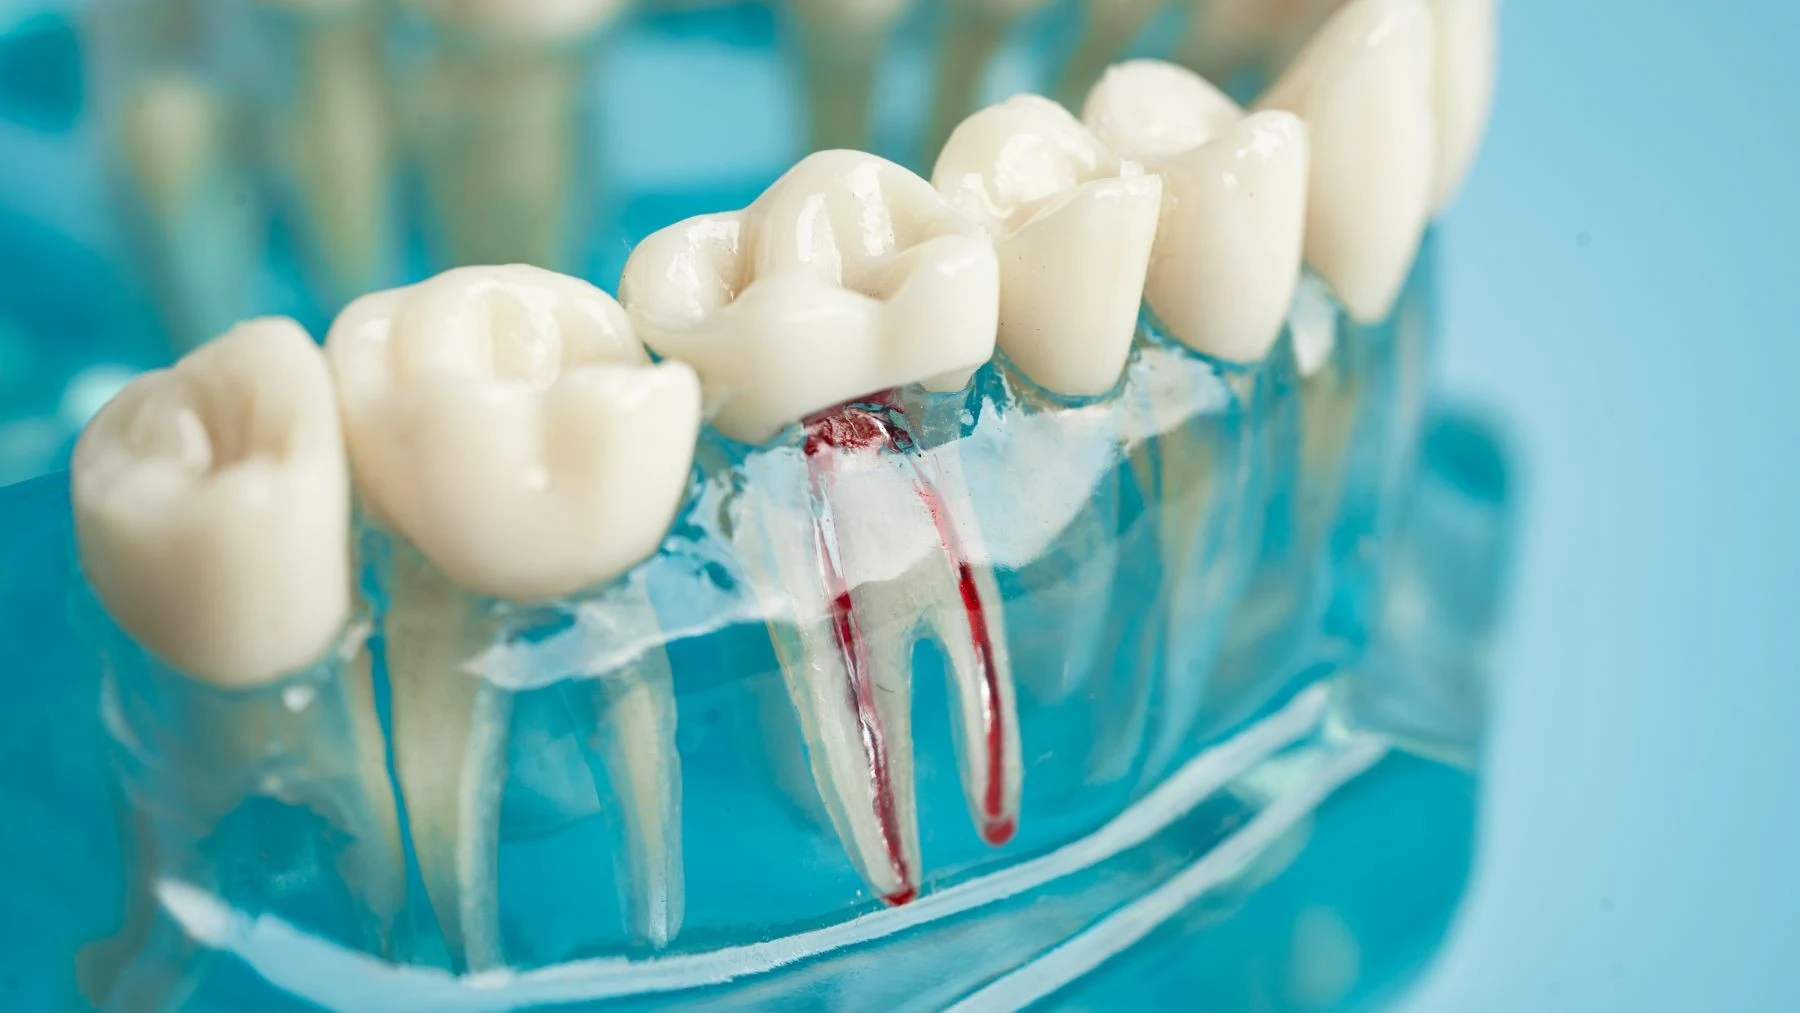

Zdjęcie RTG pokazuje, że kanał istnieje. Tomografia CBCT pokazuje, ile kanałów naprawdę jest, gdzie biegną, gdzie się rozgałęziają i czy zmiana periapikalna obejmuje wyłącznie wierzchołek korzenia – czy sięga głębiej. Tomografia CBCT zębów to badanie trójwymiarowe dedykowane diagnostyce endodontycznej, ocenie zmian okołokorzeniowych, resorpcji korzeni i lokalizacji zębów zatrzymanych. Jeden plik DICOM dostarcza danych, których żadna projekcja 2D nie zastąpi. Umów diagnostykę CBCT i uzyskaj pełny obraz sytuacji klinicznej przed decyzją o leczeniu.

Standardowa diagnostyka obrazowa w stomatologii opiera się na zdjęciu pantomograficznym (OPG) i zdjęciach celowanych (periapikalnych). Oba badania są płaskie – projicują trójwymiarową strukturę zęba na dwuwymiarową kliszę lub sensor cyfrowy. Zachodzące na siebie struktury anatomiczne, skrzywienie korzenia w płaszczyźnie niewidocznej dla prześwietlenia, zmiany periapikalne o małej gęstości lub torbiel rozwijająca się wolno bez wyraźnej destrukcji korowej – wszystko to może pozostawać niewidoczne przez wiele wizyt na diagnostyce 2D.

Tomografia CBCT zębów z małym polem widzenia (small FOV, 4x4 cm do 8x8 cm) rejestruje wybrany ząb lub grupę zębów w trójwymiarze z rozdzielczością woksela 0,08–0,2 mm. Lekarz ogląda ząb w trzech płaszczyznach jednocześnie: oralnie (aksjalnie), proksymalnie (strzałkowo) i z boku (koronowo). Anatomia kanałów, zasięg zmiany, relacja do blaszki korowej czy nerwu zębodołowego – wszystkie te dane dostępne z jednego małego pola widzenia przy minimalnej dawce promieniowania.

Anatomia układu kanałowego zębów jest zmienna w stopniu, który od dziesięcioleci zaskakuje klinicystów. Standardowy schemat – jeden kanał w przednim, dwa lub trzy w bocznym, trzy lub cztery w trzonowym – to uproszczenie statystyczne. W praktyce klinicznej trzonowiec szczęki może mieć cztery lub pięć kanałów, dolny siekacz często kryje dwa kanały schodzące się lub biegnące równolegle, a mezjalne korzenie dolnych trzonowców bywają skręcone w płaszczyźnie policzkowo-językowej z zakrzywieniem niewidocznym na projekcji bocznej.

Tomografia CBCT zębów z małym polem widzenia pokazuje układ kanałowy bezpośrednio: lekarz widzi liczbę kanałów, ich wzajemną relację, kąt skrzywienia w każdej z trzech płaszczyzn i odległość wierzchołka od anatomicznych struktur granicznych. Dla zębów wymagających powtórnego leczenia kanałowego CBCT ujawnia miejsca, gdzie poprzednie leczenie nie dotarło – boczne odgałęzienia, nieuzbrojone kanały, ślepy zaułek pominięty w pierwotnym leczeniu.

Zdjęcie RTG celowane (periapikalne) to płaska projekcja 2D – projicuje trójwymiarową strukturę zęba na dwuwymiarowy obraz, przez co struktury leżące przed i za sobą nakładają się. CBCT zębów rejestruje wybrany ząb lub sektor w trójwymiarze: lekarz ogląda go w trzech prostopadłych przekrojach jednocześnie, bez nakładania się struktur. Widoczna jest rzeczywista liczba kanałów, skrzywienia w obu płaszczyznach, zasięg zmiany periapikalnej w milimetrach i relacja do kanału nerwowego lub dna zatoki. Te dane są fizycznie nieobecne na projekcji 2D – nie chodzi o wyższą rozdzielczość tego samego obrazu, lecz o inny wymiar informacji. Zdjęcie celowane pozostaje pierwszym badaniem z wyboru ze względu na minimalną dawkę i koszt; CBCT zlecane jest, gdy dane 2D nie wystarczają do decyzji klinicznej.